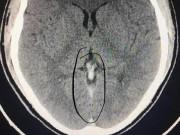

Khi nồng độ CO2 từ 3% bắt đầu gây khó thở, từ 8% đến 10% có thể gây mất cảm giác và chết người. Các triệu chứng tổn thương khi bị ngạt khí, nếu nhẹ sẽ có biểu hiện thở dốc, buồn nôn, đau đầu; ở mức độ trung bình, nạn nhân cảm thấy đau đầu dữ dội, chóng mặt, rối loạn thần kinh, buồn nôn, ngất xỉu; nặng sẽ bị ngất, hôn mê, co giật, loạn nhịp tim, trụy mạch và tử vong.